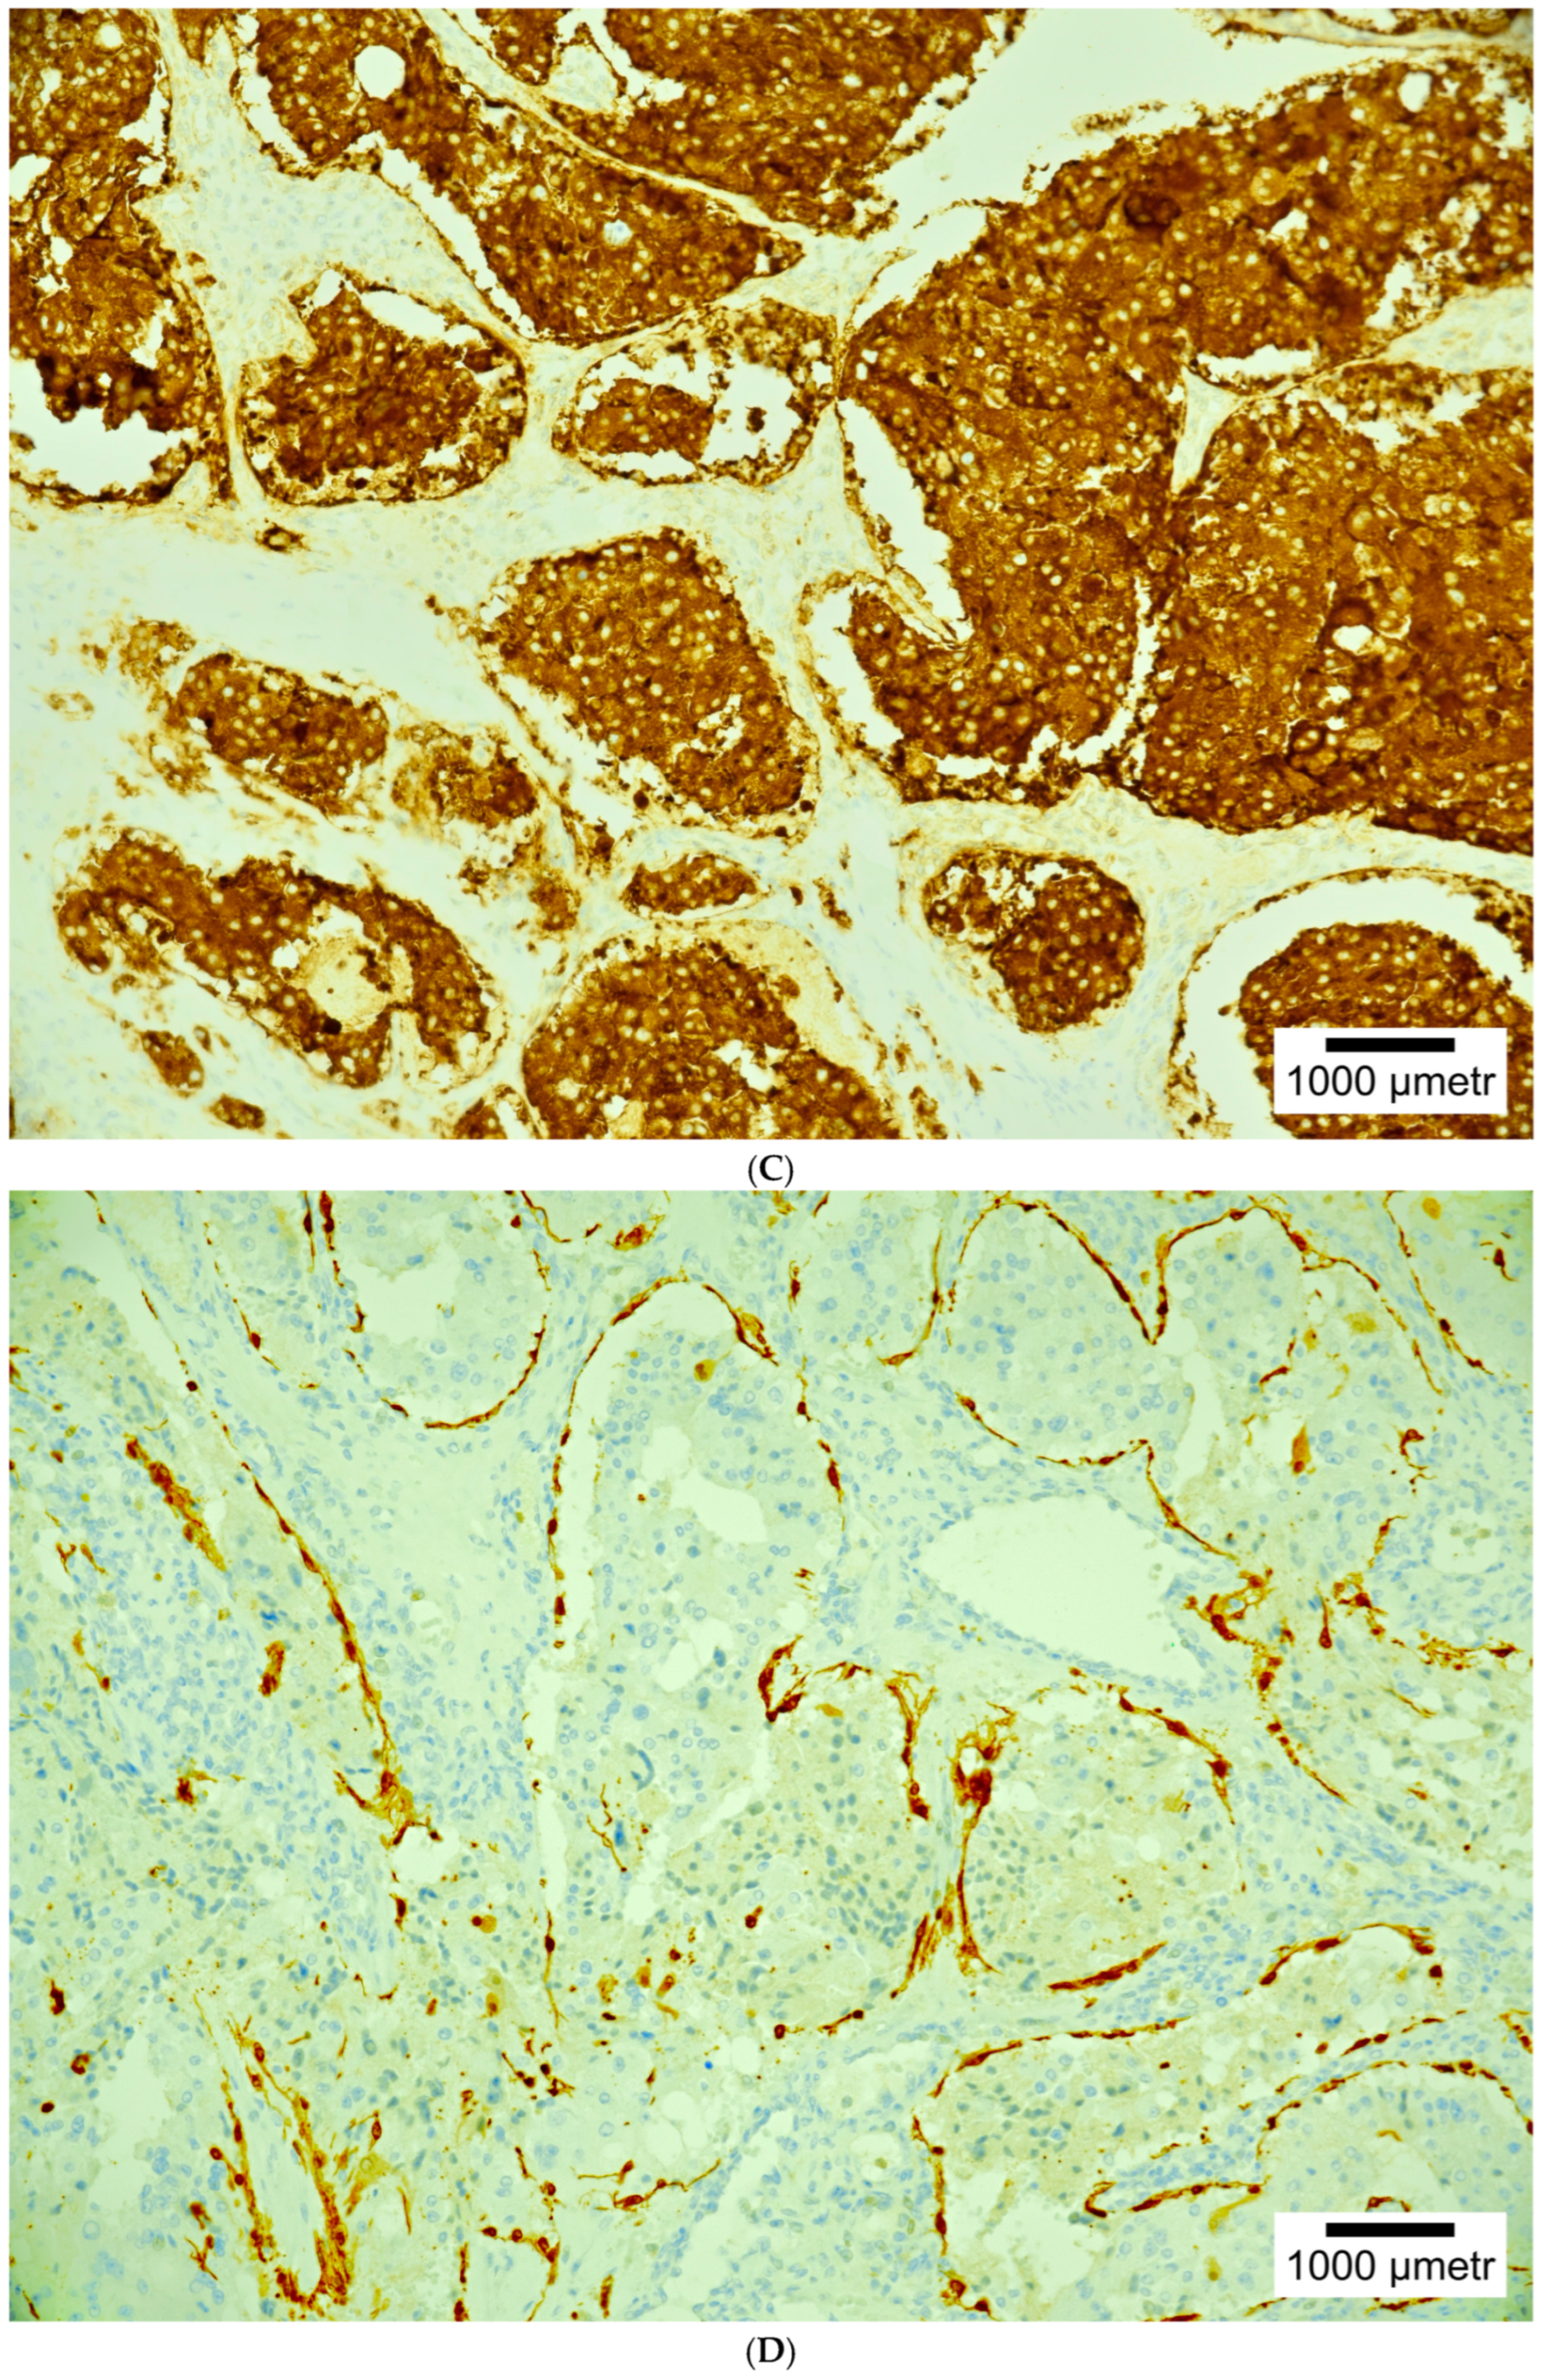

4. Histopathology